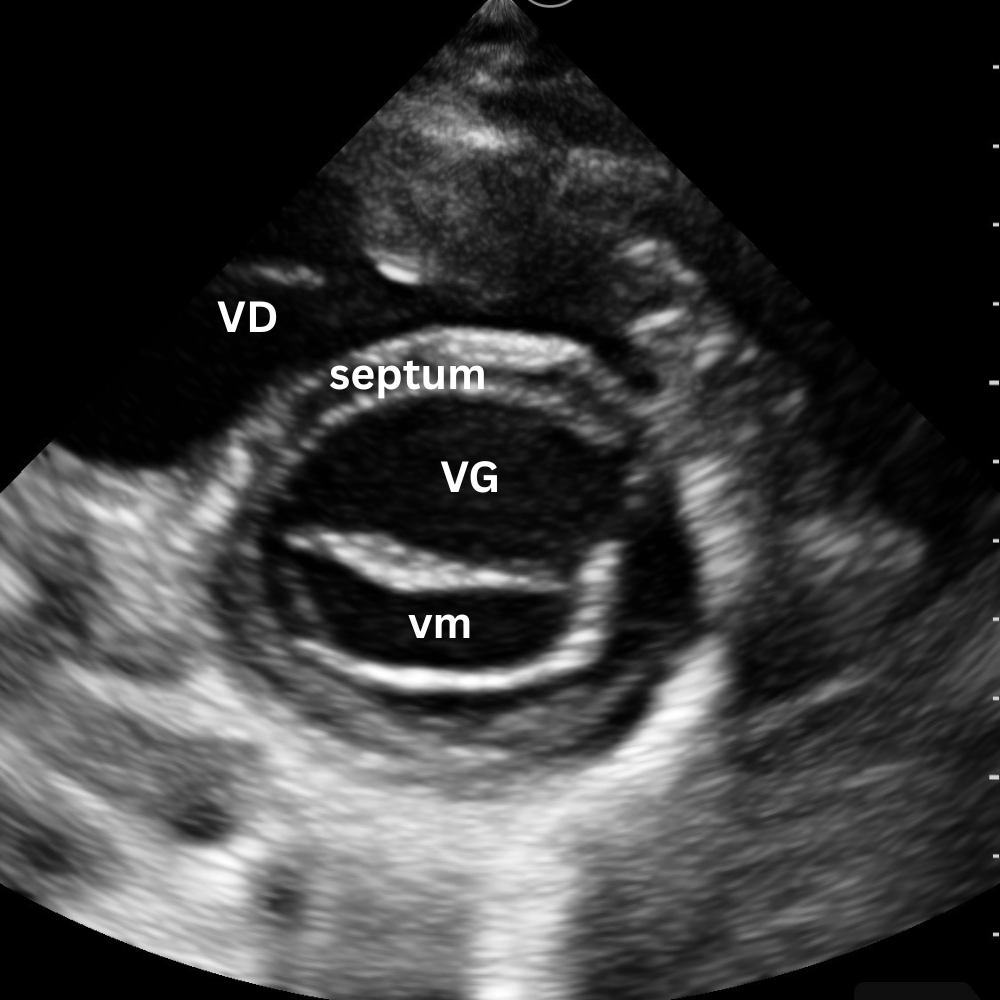

🔹 Vue Parasternale Petit Axe

→ La contraction est-elle harmonieuse ?

Même point d’appui que pour le parasternal grand axe, rotation à 90°, marqueur vers l’épaule gauche.

On observe la coupe circulaire du VG et du VD.

Un VG rond, contractile et homogène = fonction normale.

Un VG aplati ou en “D” = surcharge droite (embolie pulmonaire, HTP, tamponnade).

Une zone hypokinetique/akinetique = ischémie segmentaire.

Vue reine pour la fonction systolique et le septum interventriculaire.

Un léger mouvement de bascule permet d’explorer trois niveaux distincts :

- le plan de la valve mitrale

- le plan des muscles papillaires

- le plan de la valve aortique avec son aspect caractéristique en « signe Mercedes ».